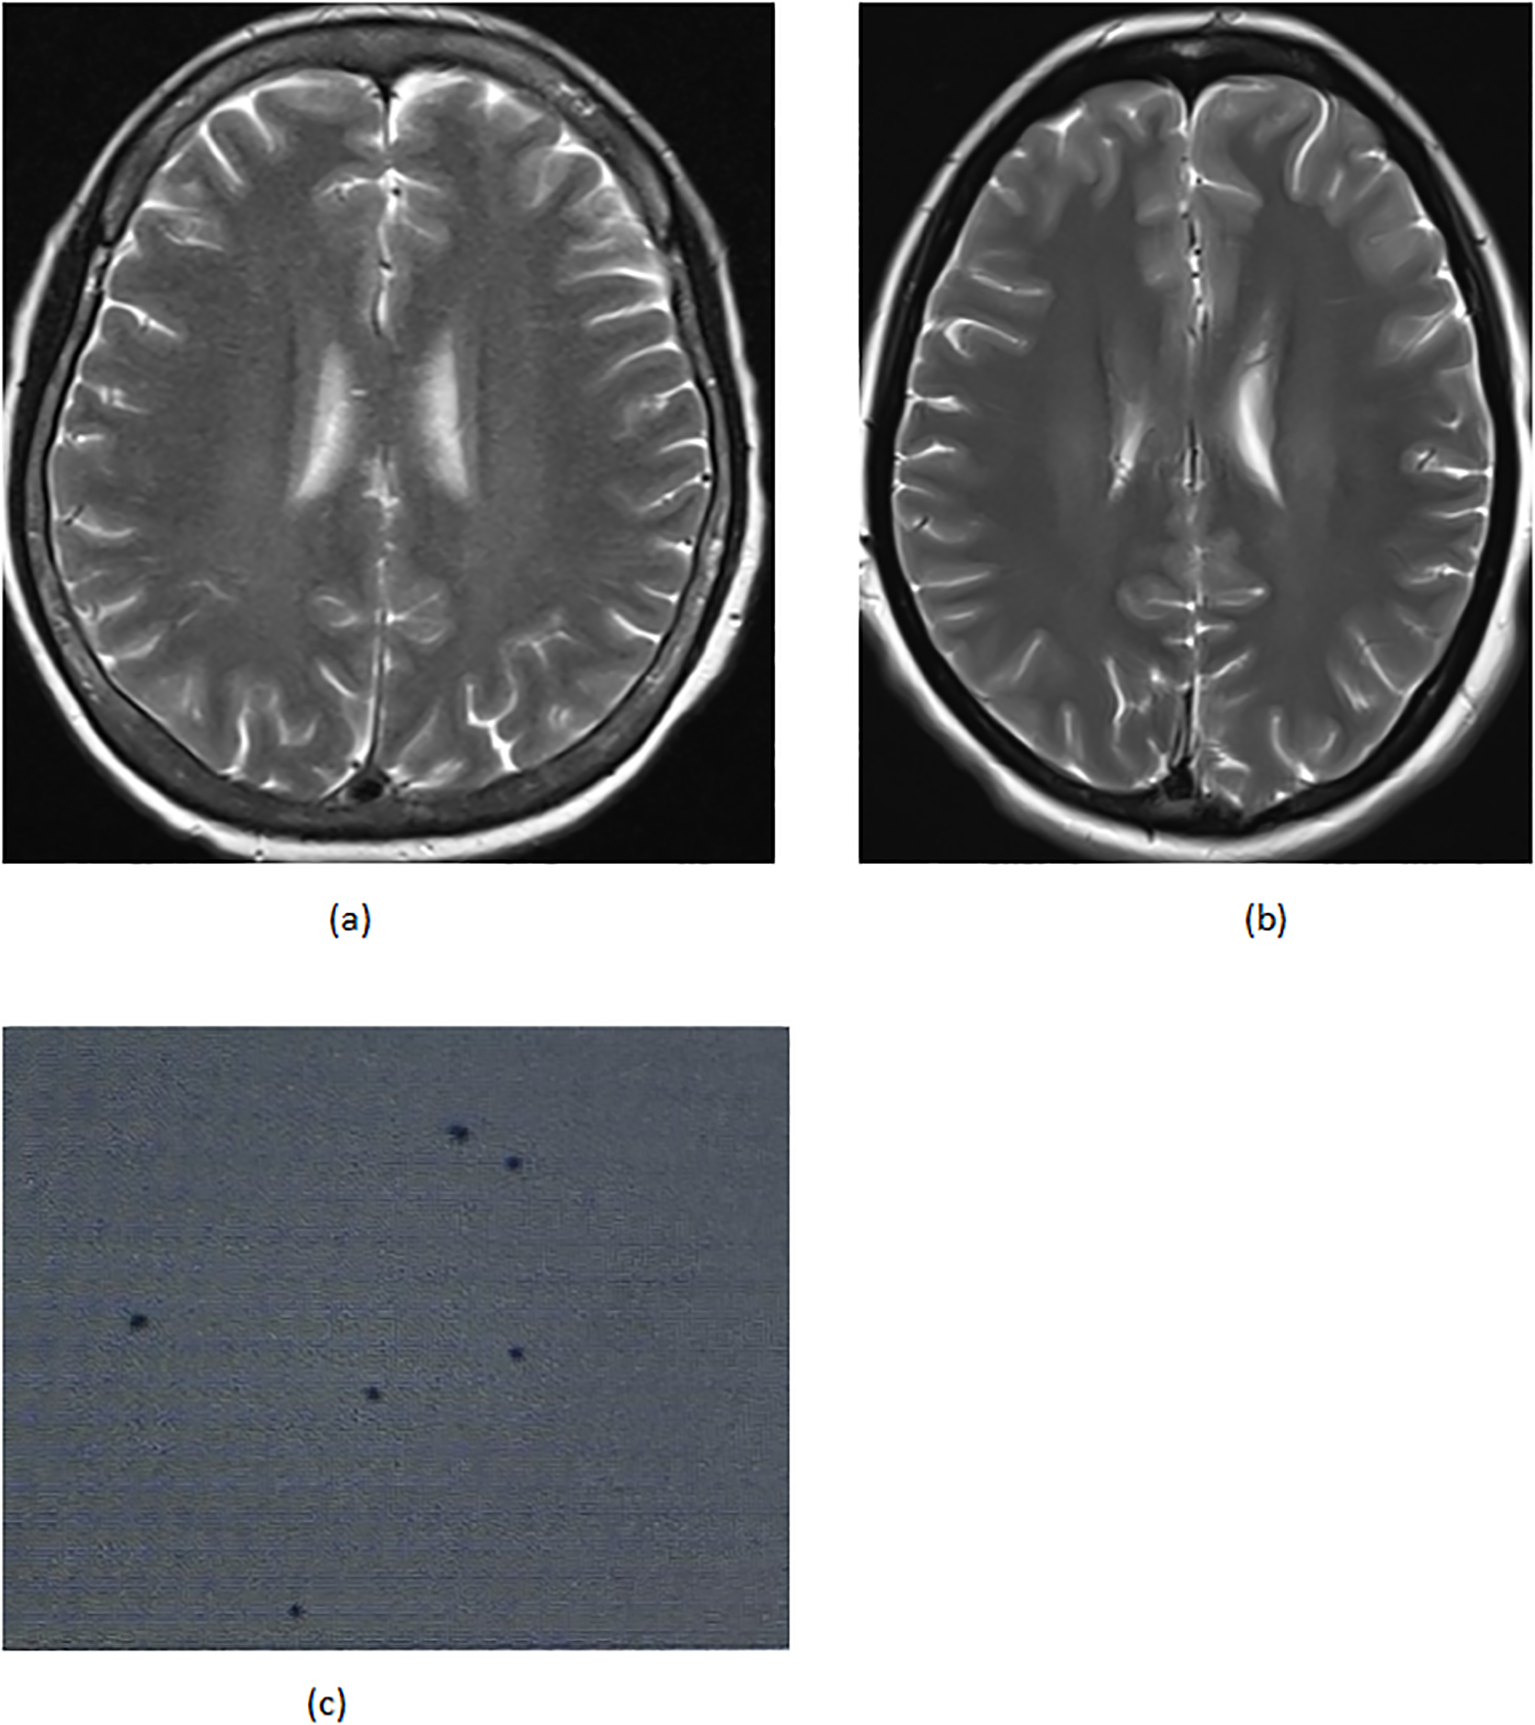

(A) 02–29 parathyroid ultrasound (B) 05-18 parathyroid ultrasound (C) 05–18 CT of the neck.

Figure 2

(A) 05–07 the brain MRI (B) 06–03 the brain MRI (C) 05–14 cerebrospinal fluid biopsy.